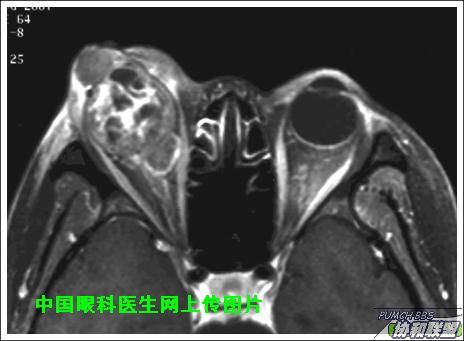

出院后半年发现右眼出现肿物,增长较快,随来京再次就诊(图1),转来我科。门诊检查发现:右眼无光感,结膜下肿物,突出睑裂。眼球突出,上移位。眶外侧可触及硬性肿物。超声(图2),CT(图3),MRI(图456)显示如图.